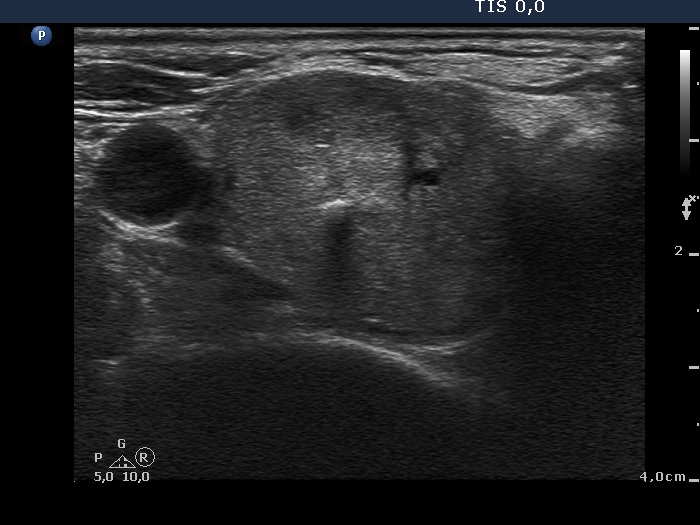

Ultrasonography: the thyroids were moderately hypoechogenic and contained several discrete, circumscribed lesions. There was a hyperechogenic nodule in the lower part of the right lobe while a cystic nodule in the upper part of the left lobe.

The thyroid is hypoechogenic and is surrounded with a relatively thin echonormal rim. This makes an appearance if both lobes were composed of a large hypoechogenic nodule. However, the echonormal rim corresponds to thickened connective tissue; a frequent phenomenon in an operated thyroid.

The upper part of the right lobe seems to be nodular, i.e. composed of two nodules at first sight. However, an insertion of the connective tissue and an acoustic shadow of a coarse calcification divides this part of the thyroid to two lesions. These do not fit nodules in a pathological sense.